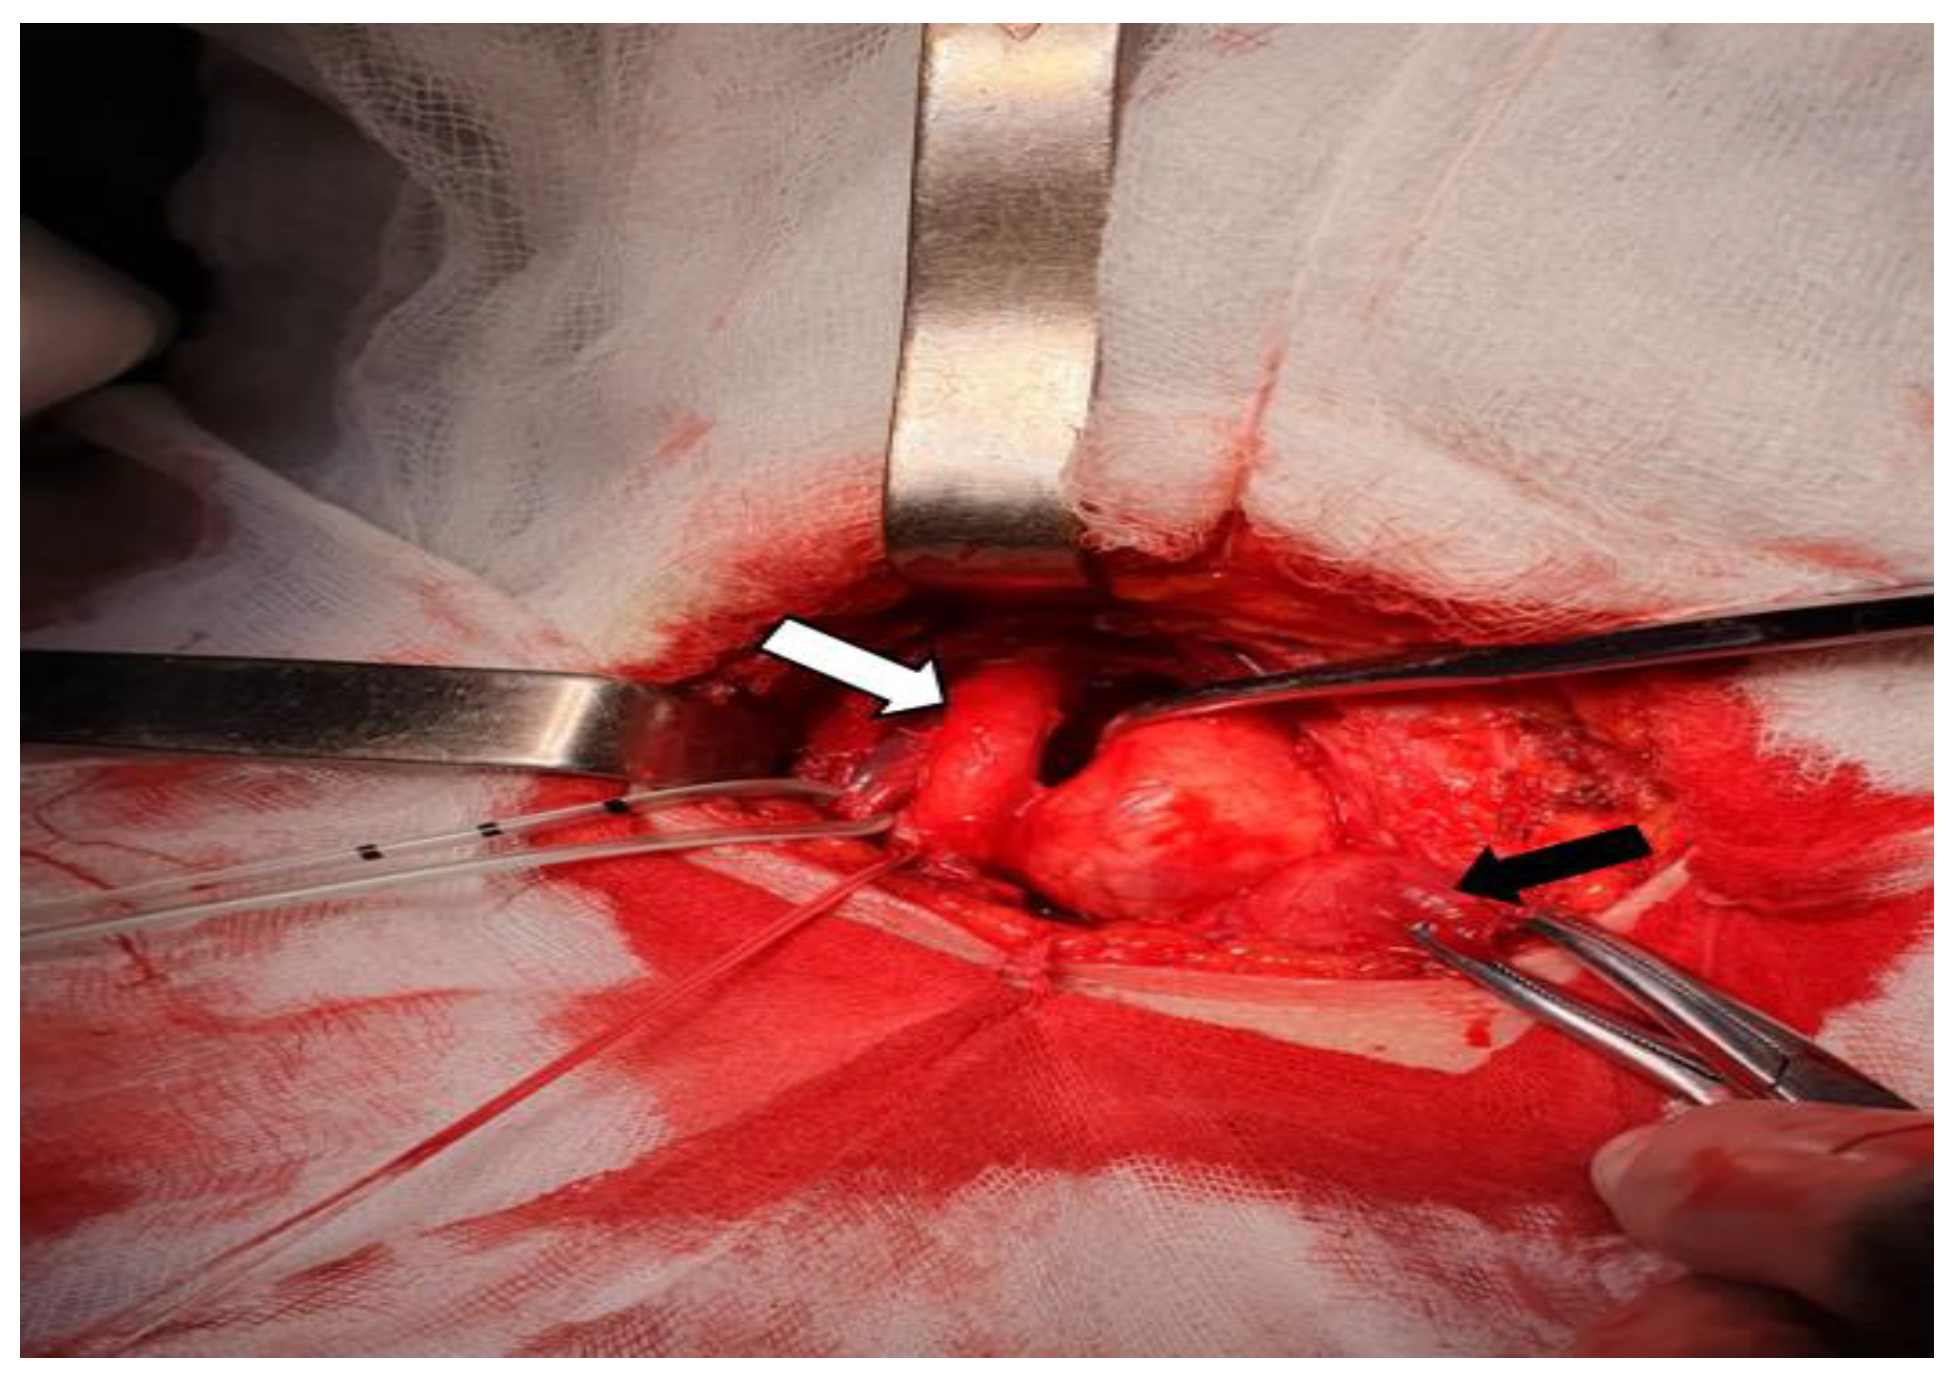

The contrast-enhanced cervical and chest CT scan showed that the mass was located in the right parapharyngeal space and had a heterogeneous structure with a weak contrast-enhancement (Figure 2A). A hypoechoic nodule was confirmed within the left thyroid lobe, measuring 17 mm in diameter (Figure 2B). The right CCA was making a 360 degrees loop in its proximal part, but did not show wall abnormalities and was patent (Figure 2C). The CT scan did not detect other cervical masses or enlarged cervical, submental or submandibular lymph nodes.

Figure 2. A. Contrast-enhanced cervical CT scan (axial plane) – right parapharyngeal space mass (white arrow) producing anterior displacement and separation of CCA (red arrow) and IJV (blue arrow); on the left side, the normal position of CCA and IJV (green arrow) B. Contrast-enhanced cervical CT scan (axial plane) – left thyroid lobe nodule (white arrow) C. Contrast-enhanced cervical and chest CT scan (sagittal plane) – the right CCA (red arrow) and the cervical tumor behind it (black arrow).